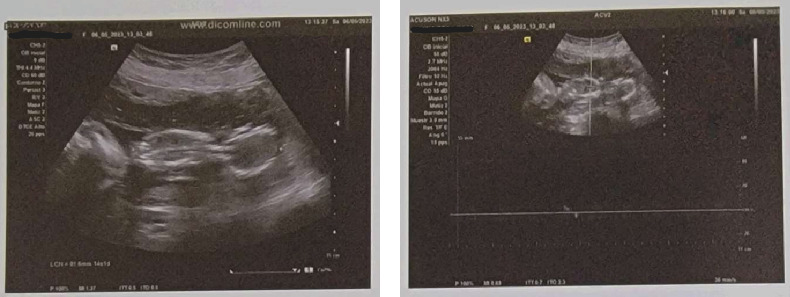

Abstract Image